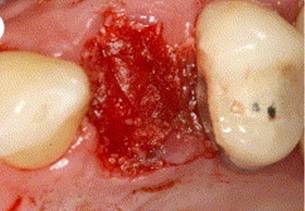

1 ST PREMOLAR EXTRACTION

BONE GRAFTING